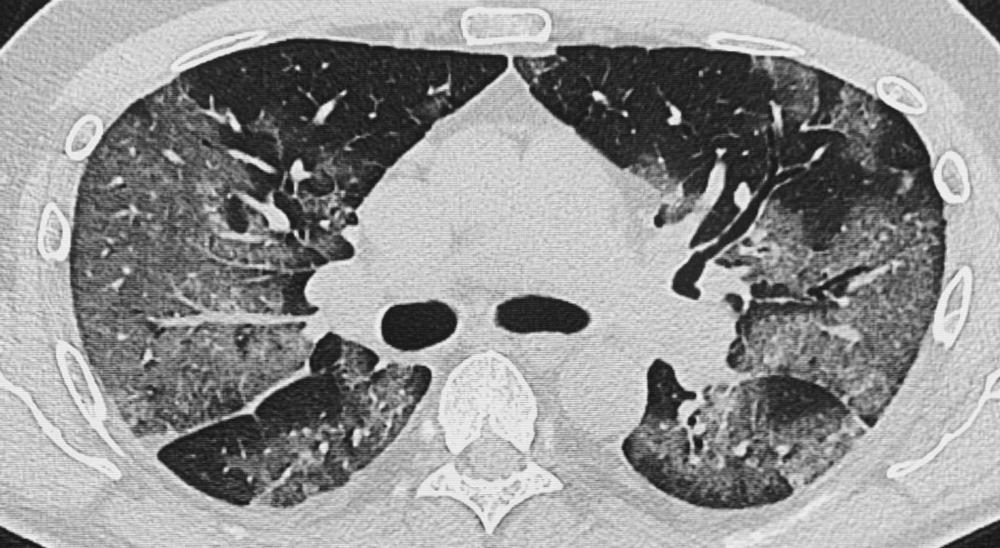

Figure 9. Chest CT images in 51-year-old male patient presenting with progressive symptoms of cough and fever, proven COVID-19. (A) Day 7 after onset of symptoms: CT demonstrates bilateral ground glass opacities (GGOs) and early vascular enlargement. (B) Day 10: Rapid progression of GGOs with vascular thickening and interstitial pulmonary edema. (Figure courtesy of Department of Radiology, Haaglanden Medical Centre, The Hague, the Netherlands.) (van Beek, et al.)

High-res (TIF) version